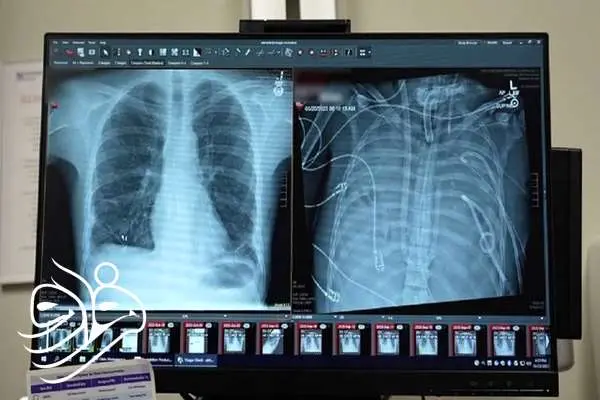

پزشکان دانشگاه نورث‌وسترن آمریکا برای نخستین بار موفق شدند مردی ۳۳ ساله را به مدت ۴۸ ساعت بدون داشتن حتی یک ریه زنده نگه دارند؛ آن هم با کمک یک سیستم ریه مصنوعی خارجی که نه‌تنها اکسیژن‌رسانی می‌کند، بلکه عملکرد طبیعی قلب را نیز حفظ می‌کند. این دستاورد می‌تواند آینده پیوند ریه را برای بیماران بدحال متحول کند.

یک مرد ۳۳ ساله بعد از اینکه گروه پزشکی، اعضای بدنش را با یک سیستم ریه مصنوعی خارجی جایگزین کردند که توسعه یافته بود تا او را زنده نگه دارند که بتواند پیوند دو ریه دریافت کند، به مدت ۴۸ ساعت بدون ریه‌هایش زنده ماند.

وضعیت تهدیدکننده حیات

قبل از قرار گرفتن روی سیستم ریه مصنوعی، این مرد دچار سندرم حاد دیسترس تنفسی شده بود که یک وضعیت اغلب تهدیدکننده حیات است که در آن ریه‌ها نمی‌توانند اکسیژن کافی جذب کنند و این مشکل توسط ویروس آنفلوانزا ایجاد شده بود. سپس او روی ونتیلاتور قرار گرفت، اما دچار عفونت مقاوم به دارو شد. این عفونت باعث شد قسمت‌هایی از ریه‌های او پر از چرک شود و او وارد شوک سپتیک شود که در این مرحله قلب و کلیه‌هایش شروع به از کار افتادن کردند.

بهارات می‌گوید: او خیلی بیمار بود، دچار ایست قلبی شد و در حال مرگ بود. از آنجا که این مرد خیلی بیمار بود که پیوند ریه دریافت کند، گروه پزشکان تصمیم گرفتند ریه‌های او را که منبع عفونت بود، بردارند.

به طور شگفت‌انگیز، مرد شروع به بهبود سریع کرد. در عرض ۴۸ ساعت، او همه داروها برای حمایت از فشار خون را کنار گذاشت، عملکرد کلیه او کاملا بازیابی شد و قلب او به طور طبیعی کار می‌کرد. در این مرحله، مرد پیوند دو ریه را دریافت کرد و سال‌ها بعد هیچ نشانه‌ای از رد عضو یا اختلال عملکرد ریه نشان نداد. اکنون تقریبا سه سال از انجام این کار گذشته است و حال بیمار واقعا خوب است.